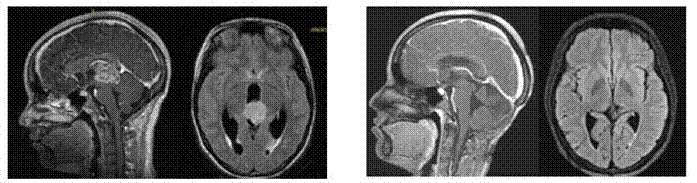

Paciente femenina de 16 años, presenta cuadro de cefalea, vomito, crisis convulsivas tónico clónicas generalizadas en junio de 2019. Se realiza estudio de resonancia (Figura 1 A) donde se observan datos de hidrocefalia y lesión en región pineal, por lo que se realizó derivación ventriculoperitoneal, se toman marcadores tumores en liquido cefalorraquídeo, los cuales resultan negativos. En el mes de agosto, se toma biopsia guiada por esterotaxia, la cual reporta astrocitoma anaplásico (Figura 2 A,B,C ). En septiembre, se somete a resección por abordaje supracerebeloso infratentorial realizando una resección total (Figura 1B). Posteriormente, se somete a 6 ciclos de quimioterapia con esquema ICE-T (Ifosfamida, carboplatino, etopósido con temozolamida) y radioterapia con 52 G y en 29 sesiones. Posterior a esto se realiza estudio de imagen de control en 2020, donde se sospecha de recidiva vs radionecrosis, concluyendo en esta última. Se decide ofrecer nuevo esquema de quimioterapia, bevacizumab e irinotecán con posterior seguimiento. En el último estudio de imagen realizado a finales de 2022, se observa libre de recidiva (Figura 1 C)

Figura 1A, Figura 1 BEstudios de resonancia magnetica de cerebro en donde se observa imagen compatible con tumoración en región pineal (Figura 1 A ) Último estudio de resonancia magnetica de diciembre 2022 en donde se evidencia presencia de tumor